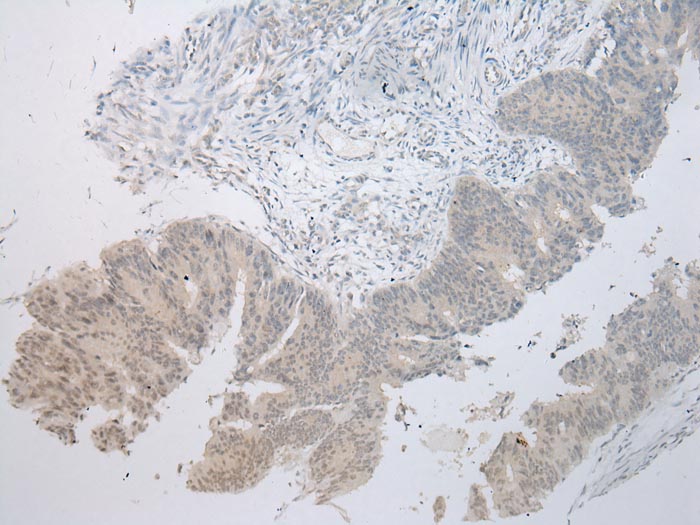

Immunohistochemical analysis of paraffin-embedded Human Colorectal cancer tissue using #43220 at dilution 1/100.